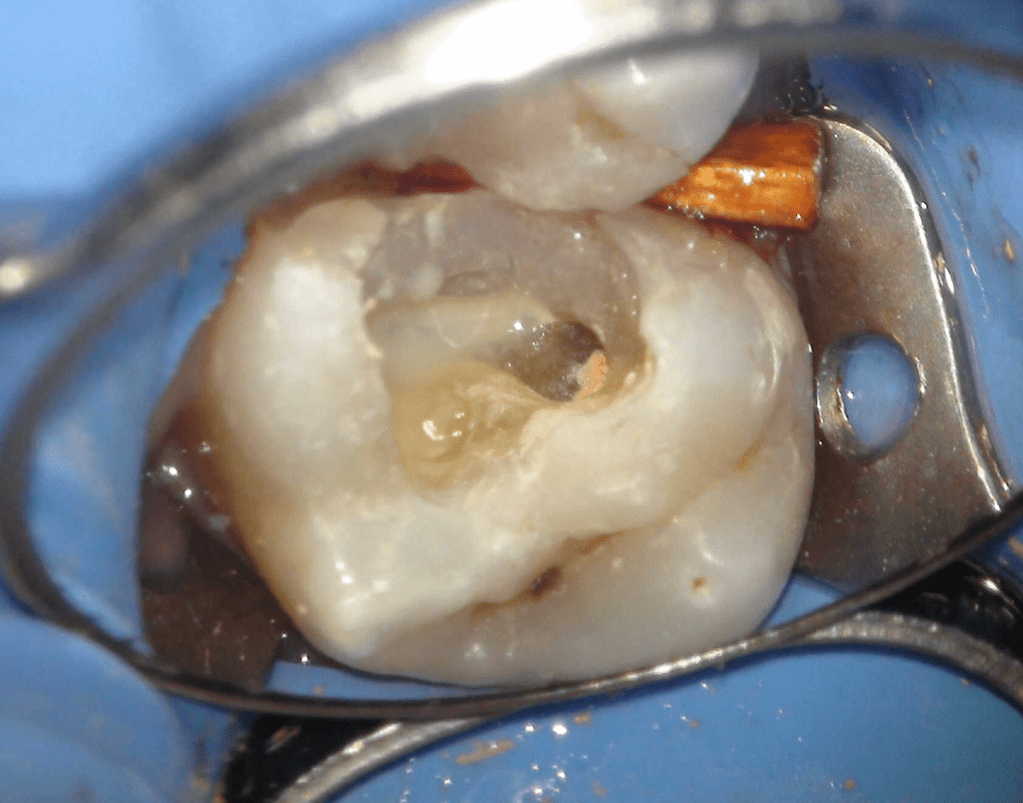

Pulpotomía biodentine + reco preendio